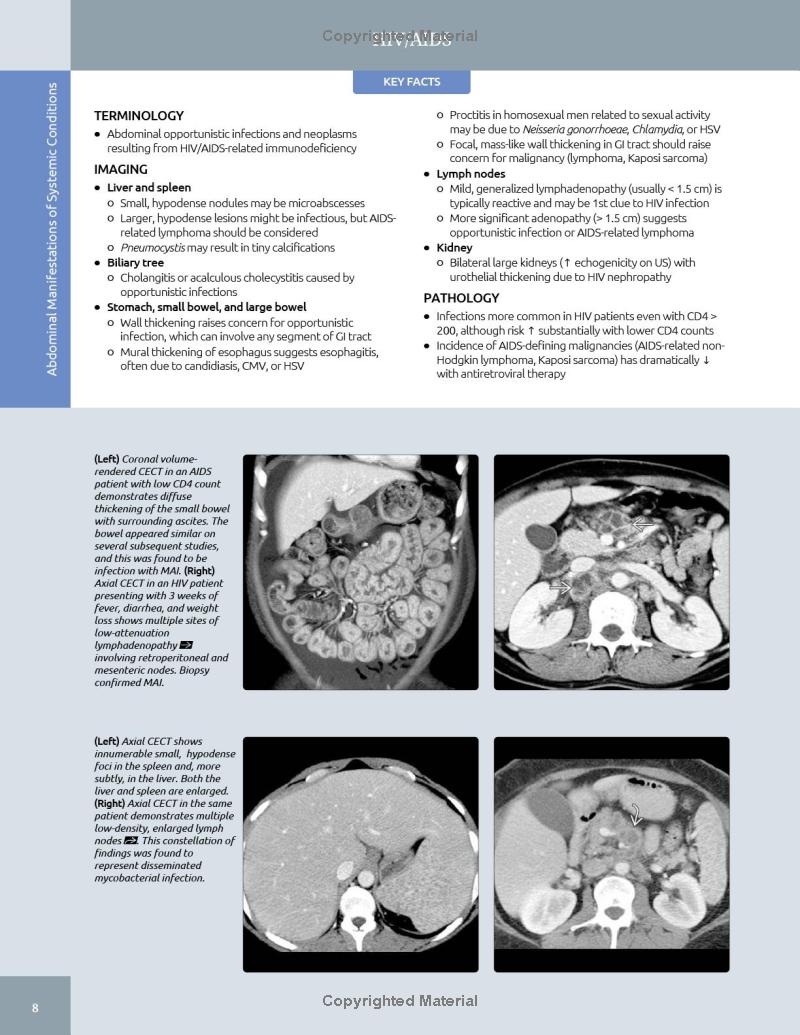

– Features more than 2,900 illustrations (multiplanar CT, sonography, MR, and PET/CT; clinical photos; radiologic images; histologic images; H&E stains; and full-color illustrations) as well as an additional 3K digital-only images and new video clips

– Covers all aspects of GI imaging, including pathophysiology, imaging findings, and disease management options such as the radiologist’s role in evaluating patients for bariatric surgery, antireflux procedures, esophageal and bowel resections, and more